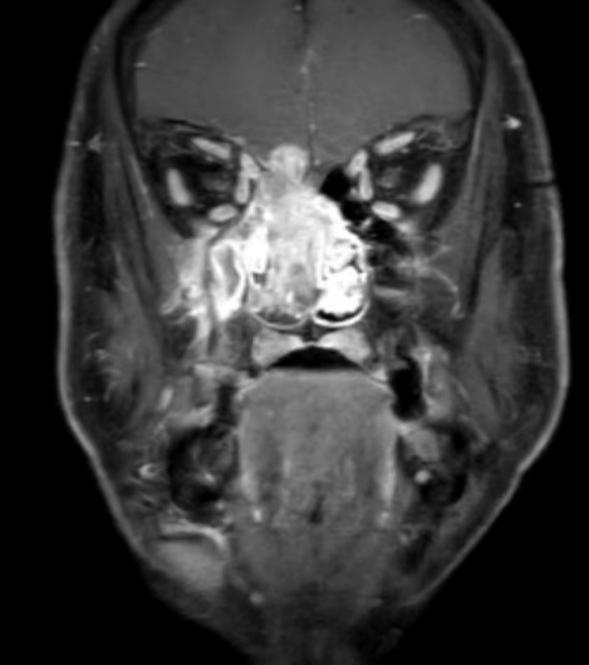

患者影像资料

患者赵某,男性,46岁,1年前开始发现右颈包块,指甲大小,未诊治。1年来包块逐渐增大增多,现大者约6*7cm,3个月前开始出现鼻塞,伴清水样鼻涕,于右鼻腔肿物取病理出血较多,病理回报:肿瘤性病变。局麻下行淋巴结活检,转移性恶性肿瘤,符合转移性高级别嗅神经母细胞瘤,磁共振见鼻腔鼻窦肿瘤似累及右侧额叶。甲状腺头颈外科二病区樊新龙医生接诊此患者,患者及家属手术愿望迫切。

患者入院后,甲状腺头颈外科二病区立即组织多学科会诊,专家组充分评估病情:患者鼻腔鼻窦恶性肿瘤,侵及前颅窝底硬膜内外,双颈淋巴结多发转移,上至咽旁,需请神经外科联合开颅手术,手术复杂、难度大,风险高。